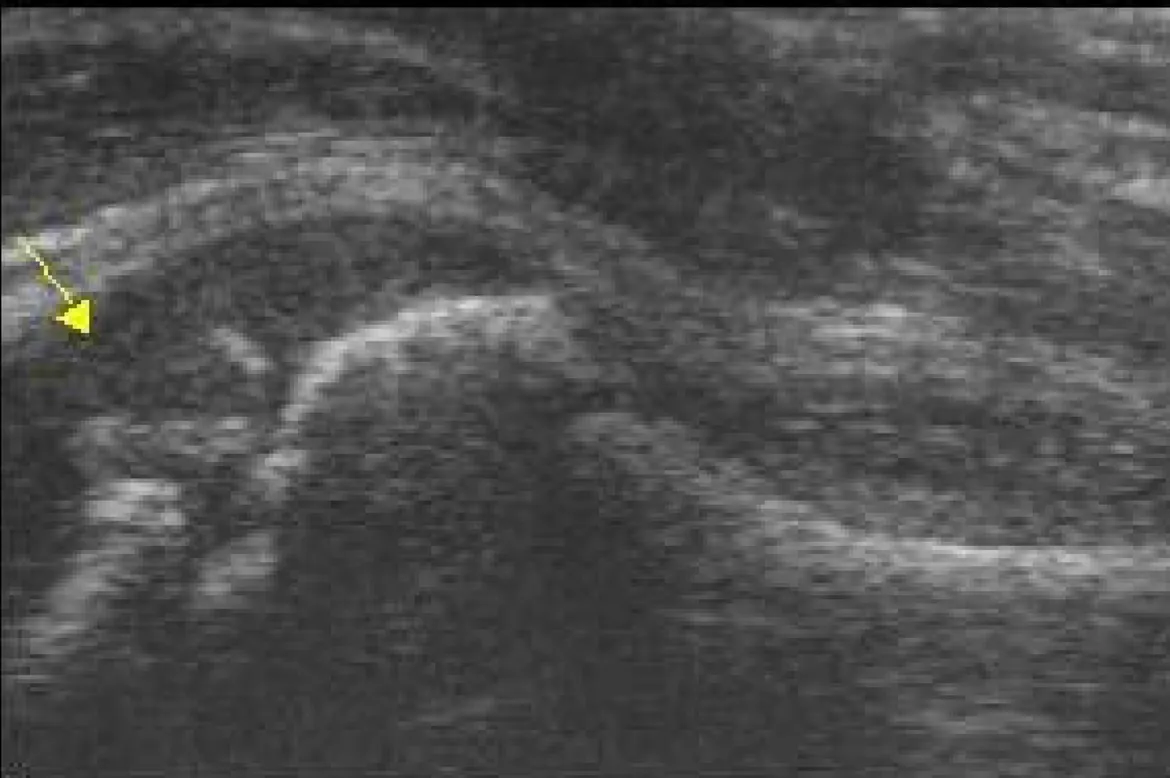

F. Slipped capital femoral epiphysis (SCFE)

(1) Ultrasound : step at the ant. physeal line

J Bone Joint Surg Br. 1991 Nov;73(6):884-9